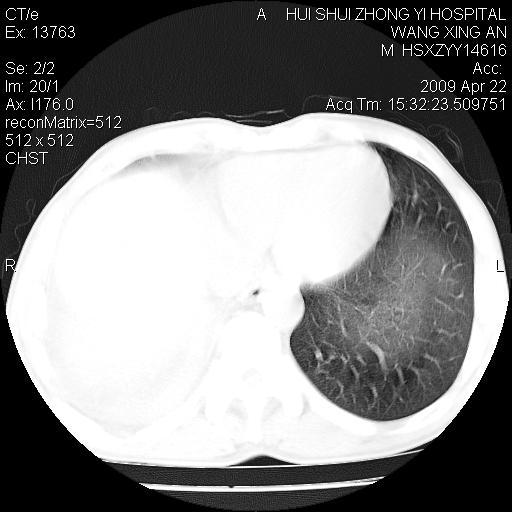

标题: CT19534:患者男、46岁咳嗽、胸痛半月。 [打印本页]

标题: CT19534:患者男、46岁咳嗽、胸痛半月。

考虑---右肺中心型肺癌继发下叶不张,少量胸水。

支持右侧中央型肺ca并右下肺不张、右侧胸腔少量积液。

1、右下肺中央型肺癌并右肺转移,右肺下叶不张。(右肺有结节影)。

2、右中上肺陈旧性肺结核(因为大多为纤维灶)。

3、右侧胸腔积液。

1、右下肺中央型肺癌并右肺转移,右肺下叶不张。(肿块围绕右肺下叶支气管生长,致管腔闭塞右肺下叶不张;右肺有结节影)。

2、右侧胸腔积液。

3、右中上肺陈旧性肺结核(右肺见纤维化病灶及点状钙化)。